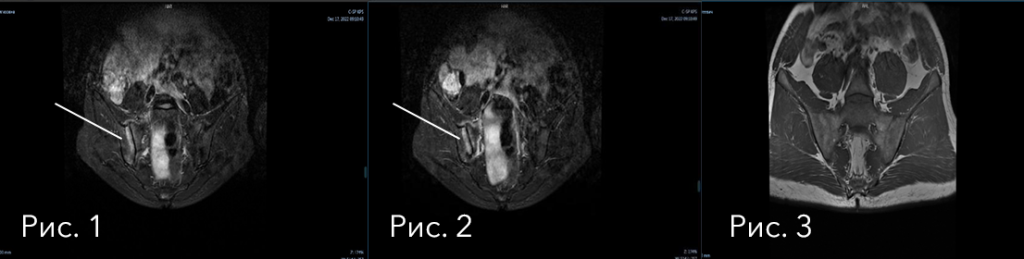

На снимках ниже (рис. 4-5), через полгода лечения генно-инженерными биологическими препаратами, мы видим абсолютную МРТ-ремиссию.